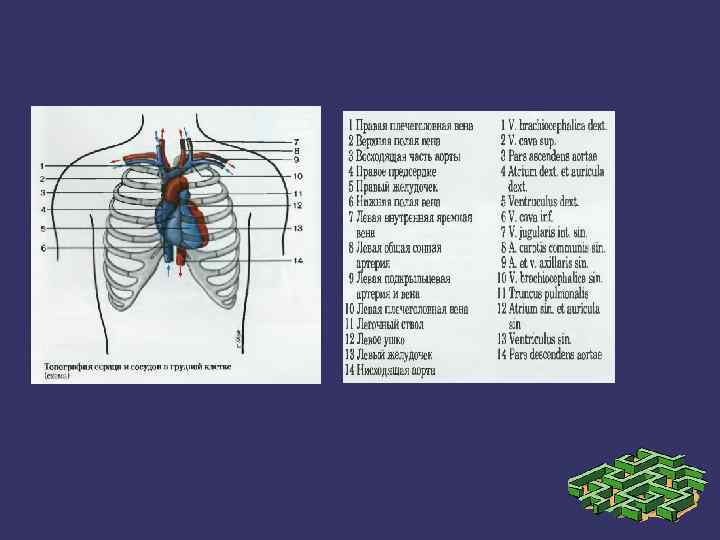

➲ ➲ ➲ Зерттеу барысында жүрек камераларының кеуде қабырғасына жатқызылуын елестетіп алуымыз керек. Оң жақ қарынша жүректің алдыңғы беткейінде орналасады. Бұл камера өкпе артериясымен кеуденің сол және артқы жағында сына тәрізді жазықтықты құрастырады. Оң жақ қарыншаның төменгі бөлігі кеуде денесінің төстің семсер тәрізді өсіндісімен байланысқан жерінен төмендеу орналасқан. Оң жақ қарынша жоғарыға қарай тарылады және III- қабырға мен төстің арасындағы шеміршек деңгейінде өкпе артериясына өтеді. Сол жақ қарынша оң жақ қарыншадан солға және артқа қарай орналасқан. Жүректің алдыңғы беткейінің кіші бөлігін ғана алып жатады. Клиникалық жағынан бұл өте маңызды, өйткені ол жұректің сол жақ бөлігін құрайды және жоғарғы серпілістің негізгі көзі болып табылады. Жоғарғы серпіліс бұл жүректің систола кезінде кеуде қабырғасына соғуын сипатайды және V қабырға арасында болады.

Митральды қақпақ (сол жақ жүрекше - қарыншалық қақпақ) төстің III қабырғамен түйіскен жерінде проекцияланады. Қолқа қақпағы төстің III қабырғаның сол және оң жақтарындағы шеміршектерінің бекіністерінің ортасынан жүргізілген сызықтың ортасында проекцияланады.

Қорытынды Қорыта айтар болсақ зерттеу барысында жүрек камераларының кеуде қабырғасына жатқызылуын елестетіп алуымыз керек. Оң жақ қарынша жүректің алдыңғы беткейінде орналасады. Бұл камера өкпе артериясымен кеуденің сол және артқы жағында сына тәрізді жазықтықты құрастырады. Сол жақ қарынша оң жақ қарыншадан солға және артқа қарай орналасқан. Жүректің алдыңғы беткейінің кіші бөлігін ғана алып жатады. Клиникалық жағынан бұл өте маңызды, өйткені ол жұректің сол жақ бөлігін құрайды және жоғарғы серпілістің негізгі көзі болып табылады. Жоғарғы серпіліс бұл жүректің систола кезінде кеуде қабырғасына соғуын сипатайды және V қабырға арасында болады.